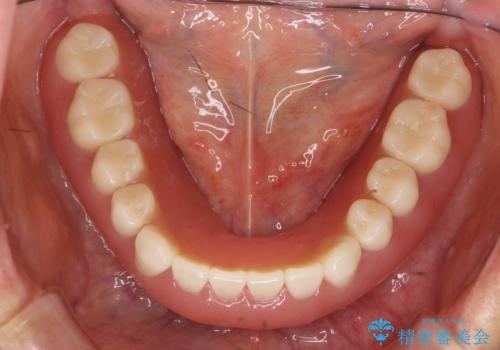

- 他院にて入れ歯を入れたが全体的に左に傾いており、咬みにくく、見た目も気になるといらっしゃった方の症例です。

診査の結果、虫歯が進行し保存できない歯が多かったため抜歯し、磁性アタッチメントを用いたインプラントオーバーデンチャーによる咬合及び見た目の改善を行いました。

磁性アタッチメントとは残っている歯根またはインプラントに磁性金属を埋め込み、入れ歯の裏側(歯肉に触れる側)に小さい磁石を埋め込んで固定させる入れ歯(義歯)のことです。土台となる歯やインプラントに無理な負荷をかけず、磁力によって強力に密着するため、ぐらついたり、ズレたりすることはありません。また総入れ歯だけでなく部分入れ歯にも使用できます。